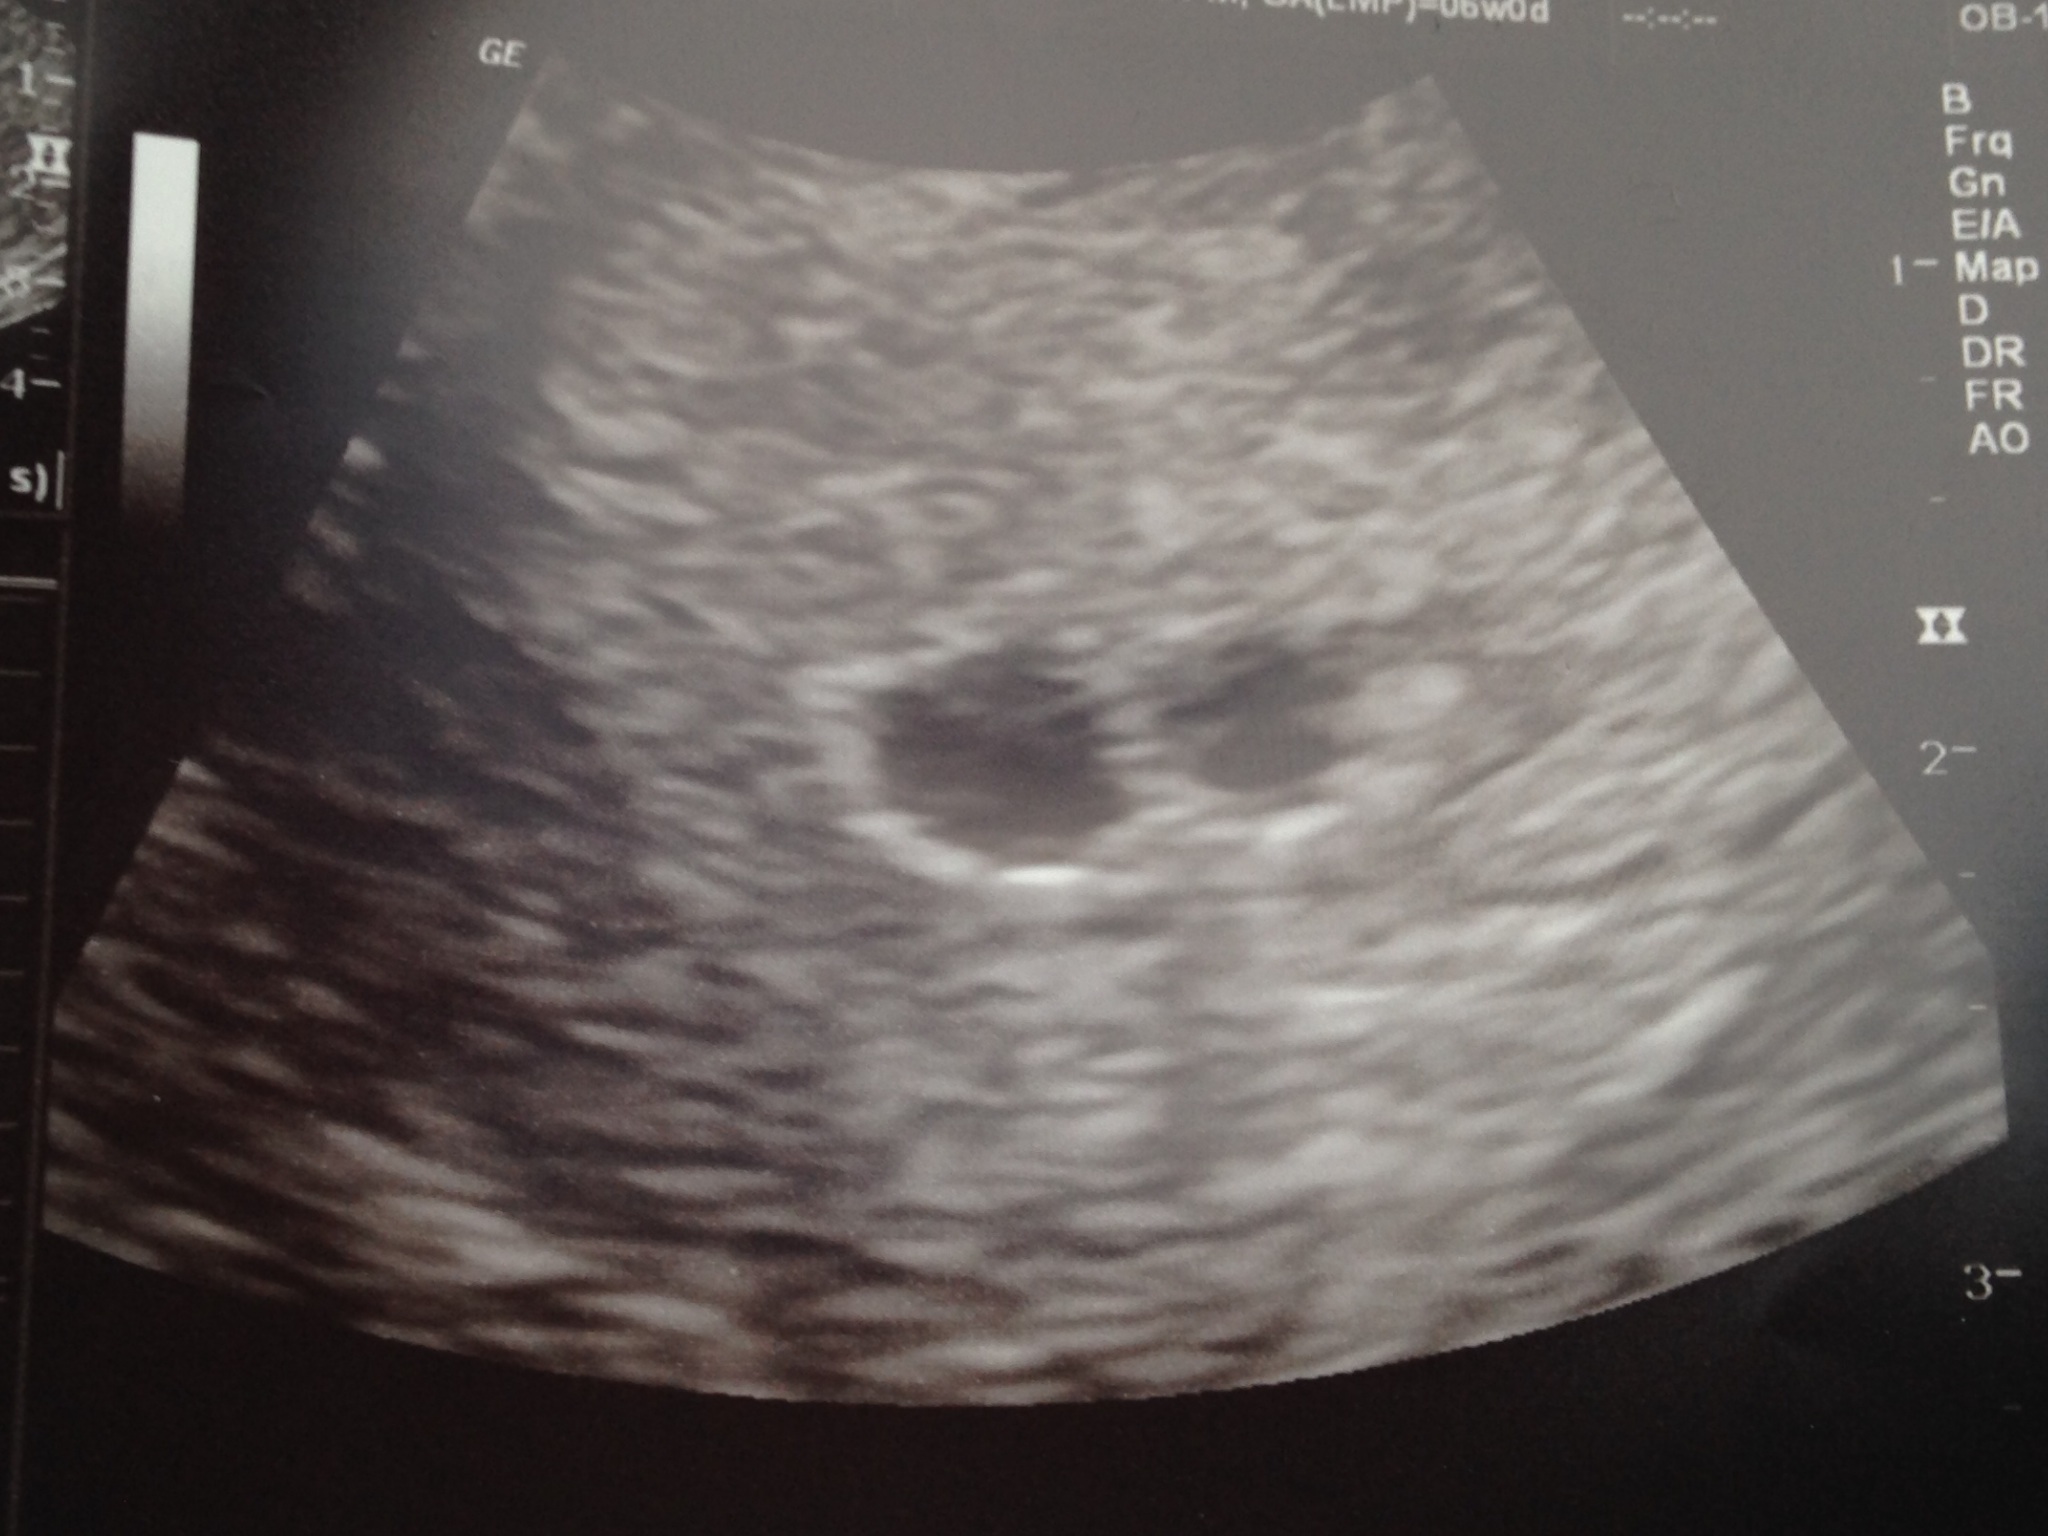

i just got back from my first appointment and am so confused. According to my lmp I should be about 7 weeks. However, I wasn't charting and have never paid attention to ovulation, so I don't know. The ultrasound was measuring behind but they didn't say how much. They did say the sac was split which could mean twins were developing or just one baby and one is a clot. I don't even know what that would mean if one side is a clot? They took blood to test my hcg and progesterone levels and will call Monday with results. I don't even know what to think about all this. Does anyone have any insights or experience with any of that? I've tried not to get overly attached yet in case something was wrong, but I do want things to work out.

I didn't get the feeling like it was ominous news, more like everyone including the doctor was confused by the u/s picture, my lmp, etc. Monday is close but seems like forever! I'm going to just be glad I have no bad signs and that my test at home tonight came out okay. Of course, I'll still worry some. I just can't even find a similar situation anywhere on google to compare!